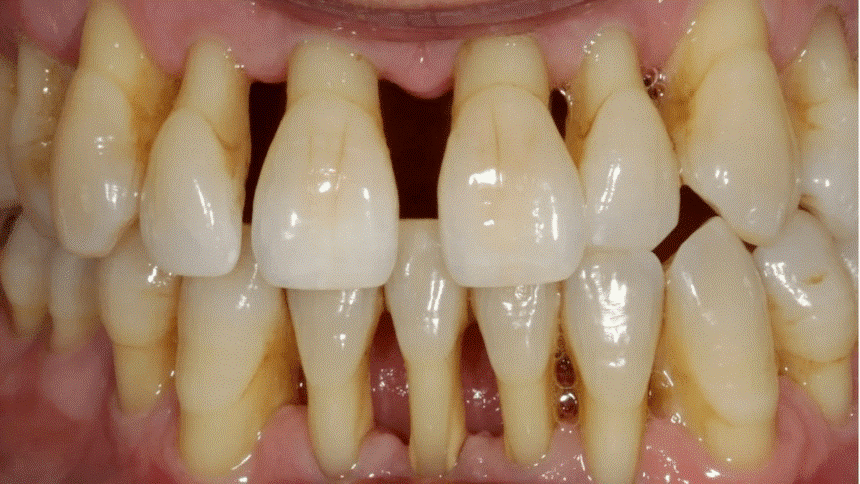

目前中老年人的牙齿疾病主要体现在四大方面:牙齿磨耗、牙龈萎缩、龋齿、牙周病。龋齿和牙周病可以说是中老年牙缺失的两大“元凶”。

(根面龋)                                                                                                           (牙周病